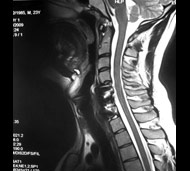

Спинальна магнітно-резонансна томографія (МРТ). Замість радіаційного випромінювання в МРТ використовуються потужні магнітні і радіохвилі для отримання зображення поперечного перерізу хребта. МРТ чітко відображає спинний мозок і нерви і забезпечує краще зображення пухлин кісток, ніж комп'ютерна томографія (КТ). Вам можуть ввести в вену кисті або передпліччя контрастну речовину, яка висвітлює деякі пухлини. Крім цього, використовують сканери з високою інтенсивністю сигналу для виявлення невеликих пухлин, які можна не помітити.